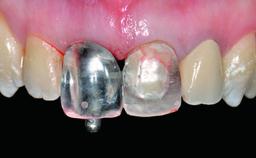

Replacement of a Failing Restored Upper Right Central Incisor, Ridge Preservation and Early Placement of an RC Bone Level Implant

A 23-year-old female, healthy and non-smoking patient had had tooth 11 temporarily restored following a trauma in adolescence. As the patient’s growth had since come to an end and the crown had fractured, she requested an implant-supported restoration of tooth 11. Moreover, the contralateral tooth 21 presented an old composite restoration at the mesial incisal edge. The periodontal tissues were healthy with periodontal probing depth values below 3 mm, but some inflammation was observed around the semi-submerged root of tooth 11.